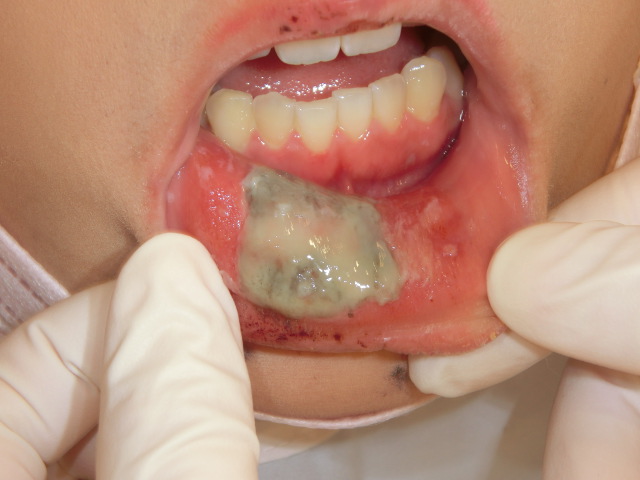

口内炎画像 (312 無料画像)

口内炎画像